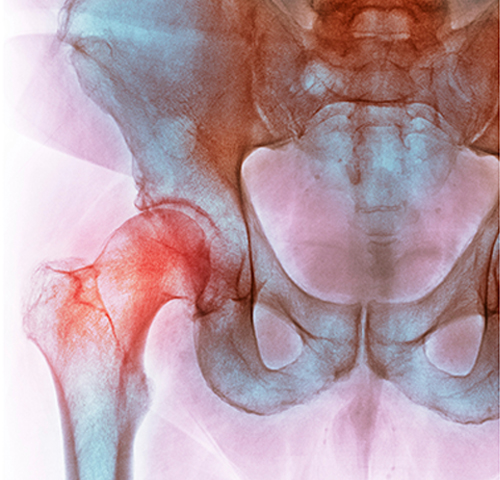

• 고관절 질환

무혈성괴사

• 정상

• 무혈성괴사

혈액순환장애로 넓적다리뼈 윗부분이 썩고 고관절이 무너지는 증상으로

조기진단이 매우 중요하며 해당부위 통증 발생 시 상담이 필요합니다.

• 무혈성괴사 진단

초기 X-ray 사진에서는 정상 소견으로 보이거나 괴사한 부분이 잘 나타나지 않는 경우가

많습니다. 이 때문에 단순 방사선 촬영만으로는 조기 진단하기 어렵습니다. 핵의학 검사나

자기공명영상(MR) 등을 활용하지 않으면 초기 단계에서 발견할 수 없습니다.

골주사(뼈 스캔) 검사는 초기 단계에서 병을 진단할 수 있지만,

MRI보다는 병변의 크기나 위치에 대한 정확도가 떨어집니다.